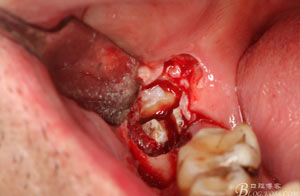

圖7.高速牙鉆去骨。逐漸可見48的牙冠

圖8.刮除牙冠表面的肉芽組織后,可見48 的牙冠